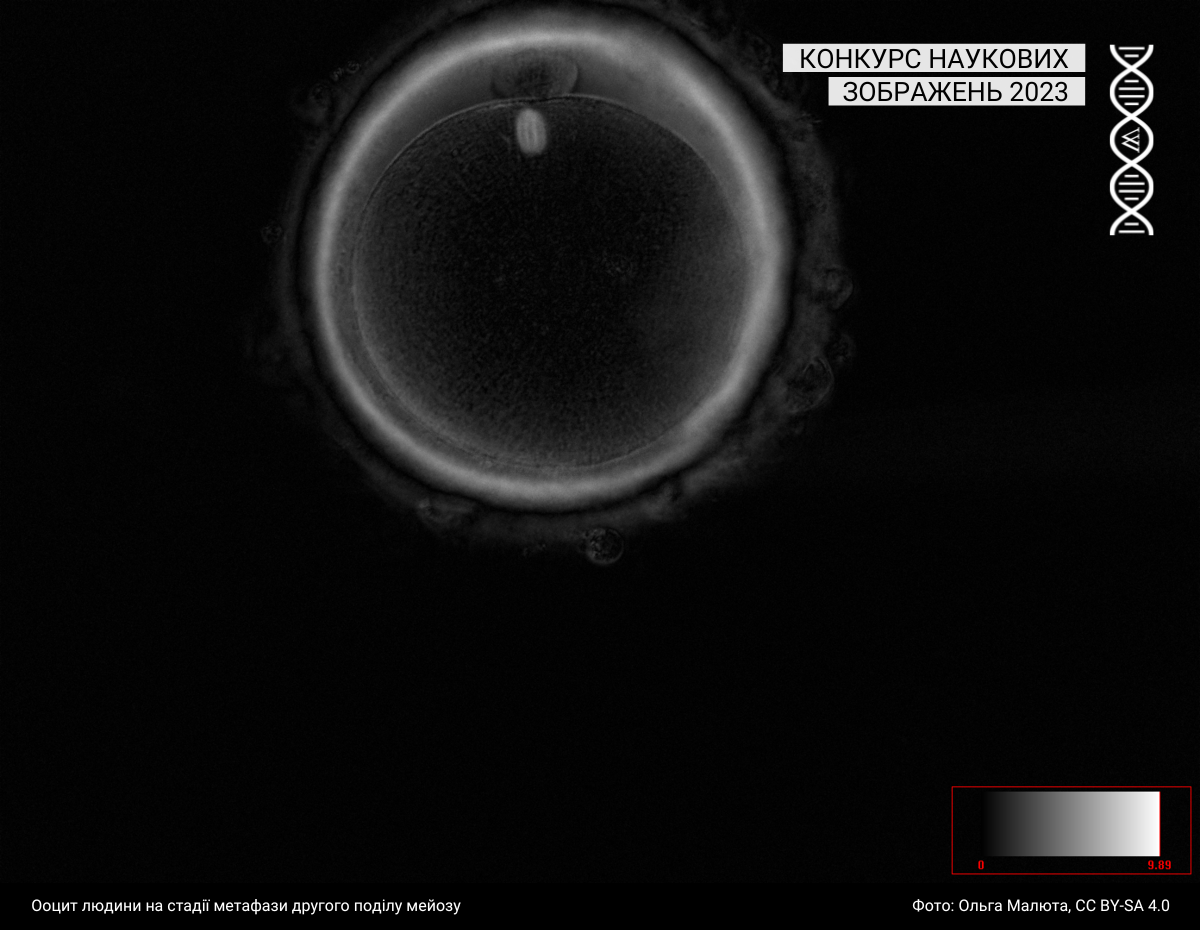

Мікроскопія

Під цю категорію підпадають світлини, зроблені за допомогою різних методик мікроскопії. Минулого року до цієї категорії учасники та учасниці завантажили 43 фотографії.

Спеціальна відзнака журі

Журі призначили спеціальну відзнаку серії зображень однієї авторки: https://w.wiki/99qJ, https://w.wiki/99qK, https://w.wiki/99qL, https://w.wiki/99qM